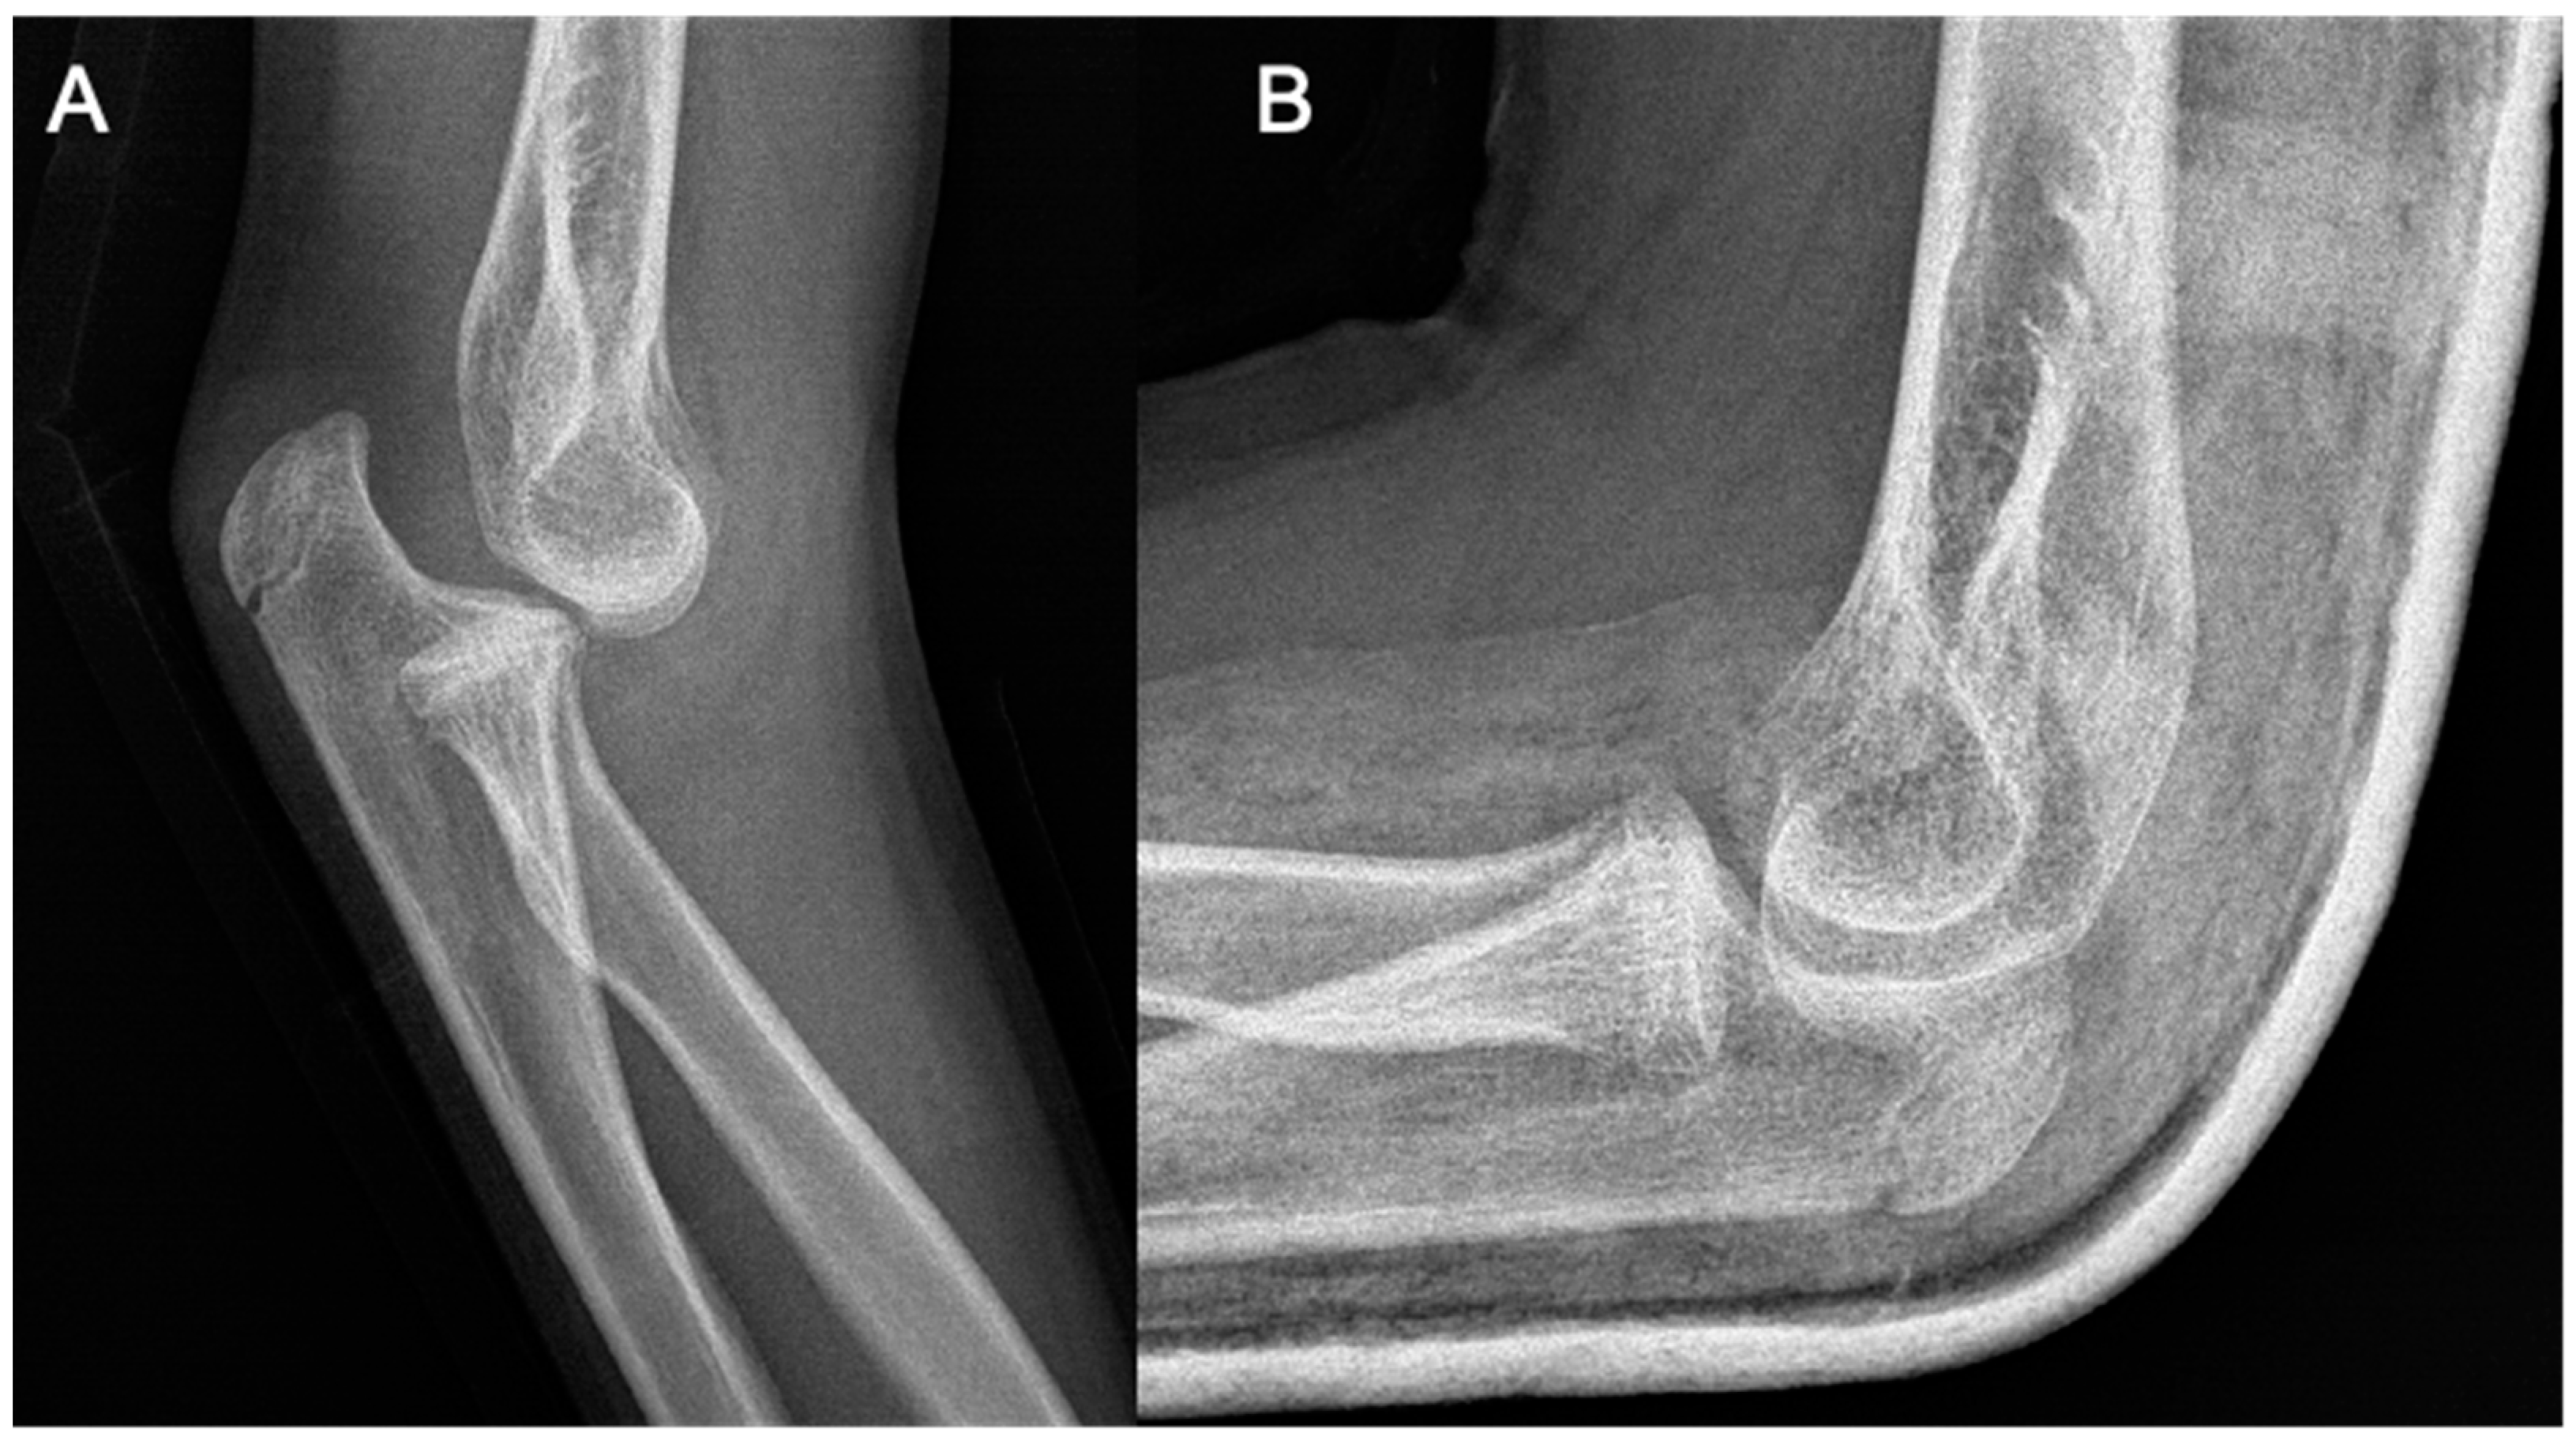

Figure 1.

Plain radiographs taken at the initial injury.